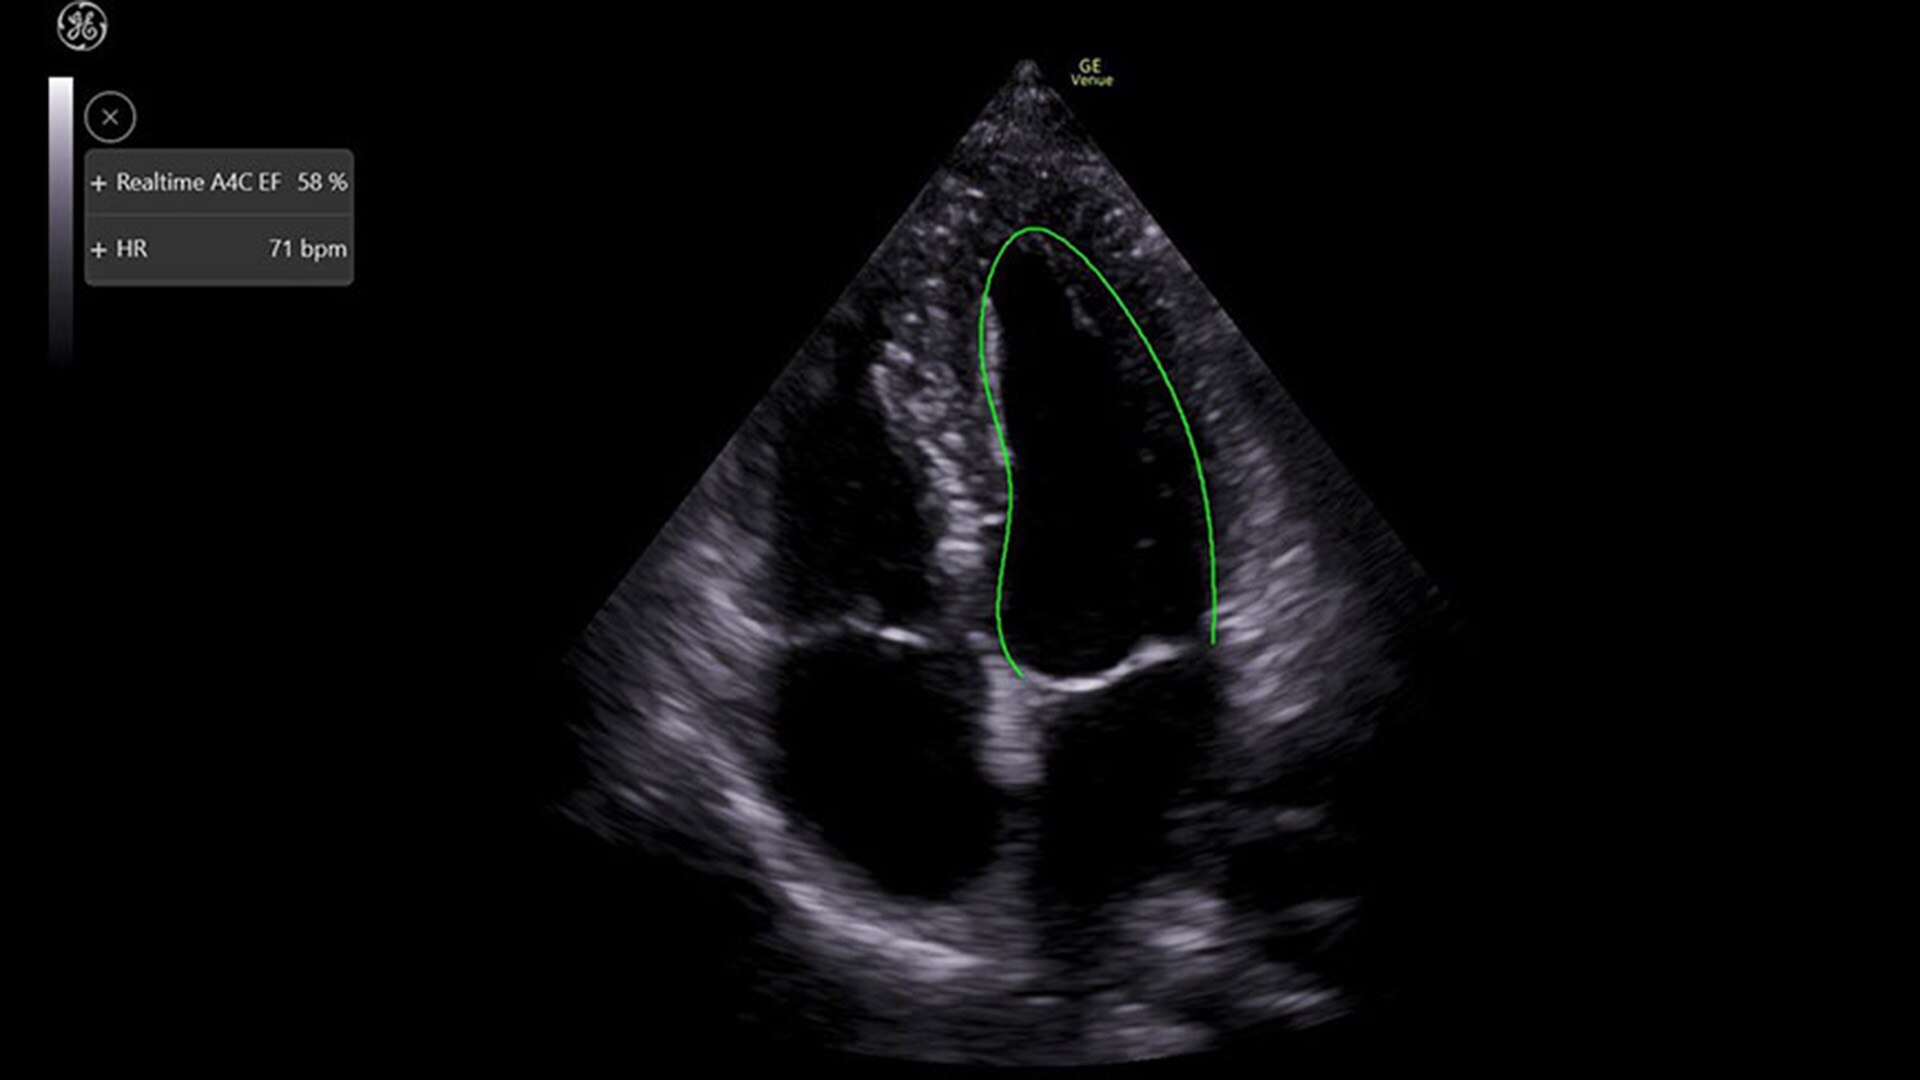

REAL-TIME EF

For accurate, instant, and rapidly updating results

Capture precise results instantly without requiring ECGs—thanks to Real-Time EF, an AI tool that continuously calculates real-time ejection fraction during live scanning in apical 4CH view. And for improved accuracy, its integrated quality indicator helps users select an optimal view for generating exacting results. Reducing the time it takes to reach a result while helping provide consistency, a study found that Real-Time EF results are within ±10 points of experts in 86% of adult cases (80% including pediatrics).2